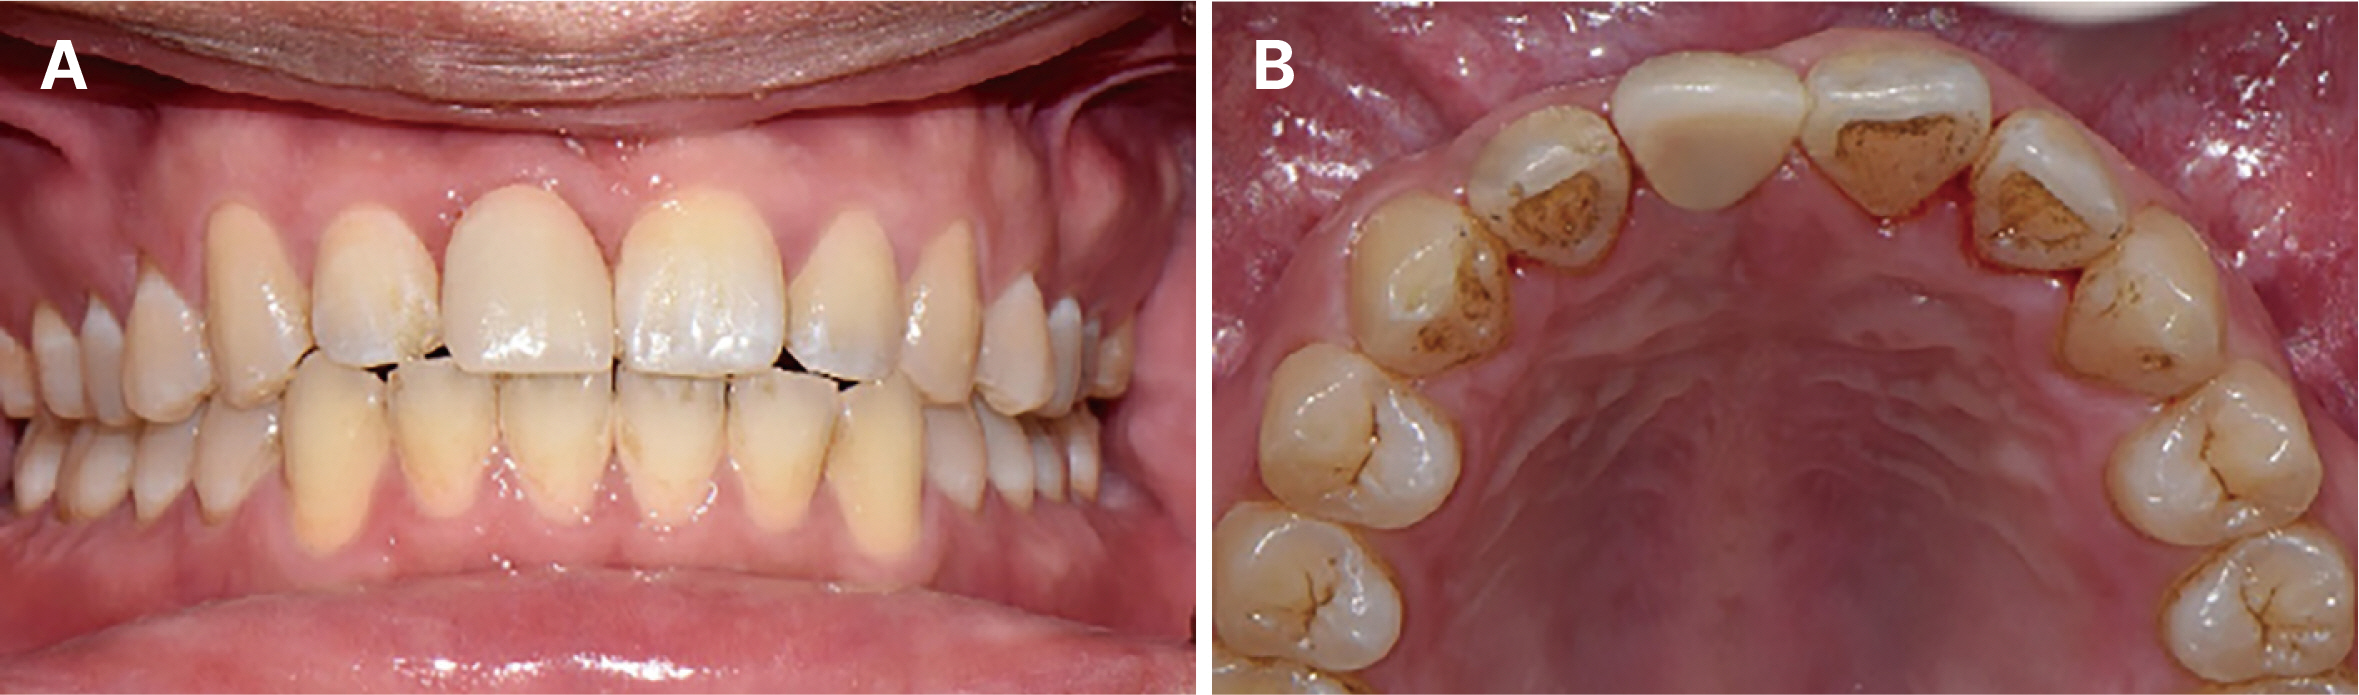

- Immediate implant placement and immediate loading in the anterior maxilla is an effective approach to rapidly address aesthetic demands. To achieve successful outcomes, bone quality, soft tissue condition, and accurate implant positioning are essential factors. For optimal results, procedures such as bone augmentation, precise implant placement, and, when necessary, soft tissue grafting should be considered. Furthermore, provisional restoration play a crucial role in achieving the desired appearance of prosthetic restorations and improving the aesthetics of the soft tissue. By performing soft tissue molding through provisional restoration, an ideal emergence profile can be established, which can be subsequently transferred to the final prosthesis, leading to a functional and aesthetically pleasing restoration. This approach aims to optimize the aesthetic outcomes in the anterior region while preserving the natural contours of the peri-implant soft tissue. In this case, a patient requiring extraction of maxillary anterior tooth underwent immediate implantation and alveolar bone grafting using a guide fabricated in advance from CT data. The patient received a provisional restoration on the same day. Subsequent steps included transitioning from the provisional prosthesis to the definitive prosthesis, ultimately achieving an aesthetically pleasing and functional implant restoration. We report this case to highlight the successful approach to maxillary anterior implant rehabilitation.